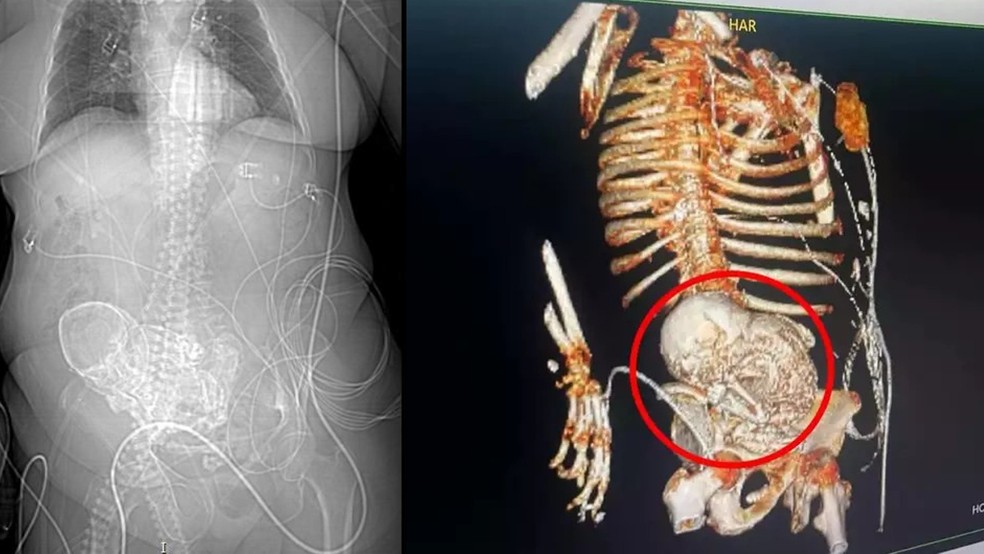

A paciente deu entrada no Hospital Regional de Ponta Porã com um quadro de infecção grave em 14 de março. No mesmo dia, uma tomografia 3D constatou o feto calcificado na região do abdômen dela.

Após a idosa dar entrada no HR de Ponta Porã, em 14 de março, uma tomografia 3D foi solicitada para precisar o diagnóstico. O exame que identificou o feto calcificado no abdômen da mulher, de acordo com as informações da secretaria de Saúde de Ponta Porã.

O secretário de Saúde de Ponta Porã, Patrick Derzi, explicou que o nome da condição é litopedia. Derzi, que também é médico, comentou que o quadro clínico da idosa é considerado um tipo raro de gravidez, que só ocorre quando o feto de uma gravidez abdominal não reconhecida morre e se calcifica dentro do corpo da mãe.

“A litopedia é um tipo raro de gravidez ectópica [tipo de gravidez quando o óvulo fertilizado se desenvolve fora do útero], e ocorre quando o feto de uma gravidez abdominal não reconhecida morre e se calcifica. O ‘bebê de pedra’ é resultante e pode não ser detectado por décadas, e pode causar complicações futuras”, comentou o secretário.